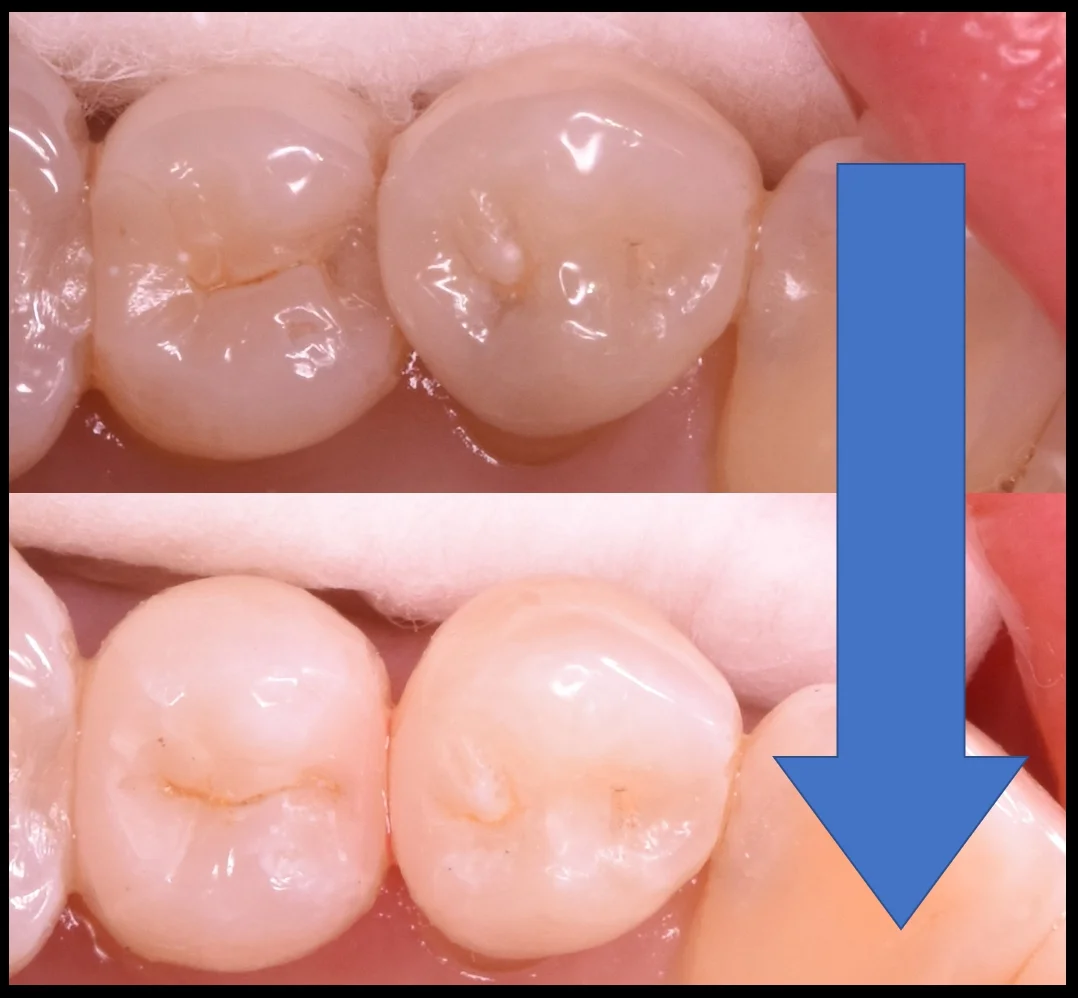

では術前の写真からです。

中央の2本の歯の治療になるのですが、後ろの歯が手前の歯に隠れているのが分かるかと思います。

これは歯の形もそうなのですが、虫歯によって出来た穴の部分に後ろの歯が食い込んでいってこうなっています。

術前術後の写真がこちらになります。

奥歯の歯並びが悪くなってしまっている所の治療|坂寄歯科医院(取手市藤代) - 画像7

ブラッシングはしやすくなったかと思いますので、これで長期予後を期待できるかと思います。